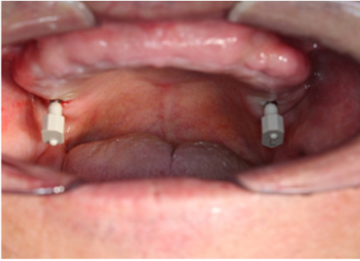

In the first case, the prosthetic rehabilitation on dental

implants in the upper arch of an edentulous male patient wearing

a total removable prosthesis is described.

The first step consists in the creation of two holes in the

removable prosthesis in the area of the maxillary second molars,

to allow the housing of the skeletal scan bodies. In each of these

sites, one mini-implant (Biotec S.r.l., Povolaro di Dueville, Italy)

combined with the skeletal scan body is placed (Figures 2 & 3).

Figure 2A: One mini-implant positioned in the left side of the maxillary arch.

Figure 2B: The two skeletal scan bodies positioned on the maxillary arch.